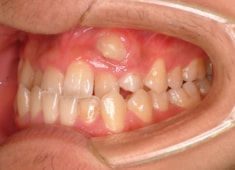

治療後(2年1ヶ月後)

下顎の右側への偏位は解消されました。

大臼歯は整直されております。

歯根のパラレリングは良好です。

左上2番の歯根も問題なさそうです。

下顎8番は保定期間に入り、しばらくして咬合が安定してから抜歯する予定です。

特に左側の咬合時の顎関節の位置に改善が認められます。